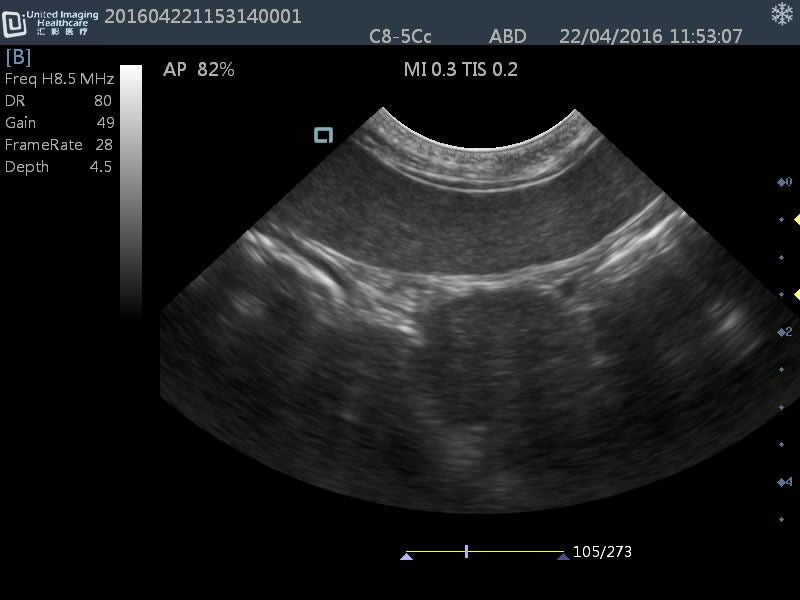

Micro-convex(R15): C8-5Cc

- Application: General small abdomen and cardiac

- Equine musculoskeletal and abdomens

- Number of element: 80

- Center frequency: 6.5MHz

- Working frequencies: 5 – 9MHz